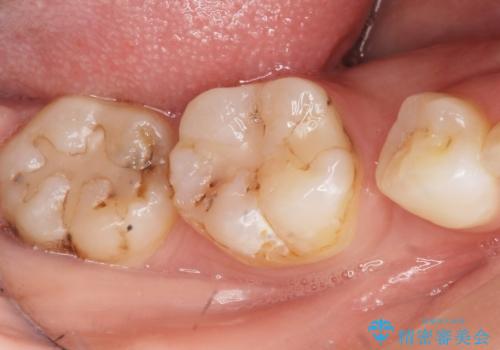

- 奥歯の隙間を治したいとご希望された患者様です。

学生時代に舌側矯正されていたものの、通院が大変になり治療を途中でやめてしまい、奥歯の間に隙間が残ってしまったそうです。

矯正せずに早く治したいという強いご希望とう蝕があることから、セラミッククラウンによる補綴治療で隙間を閉じることにしました。